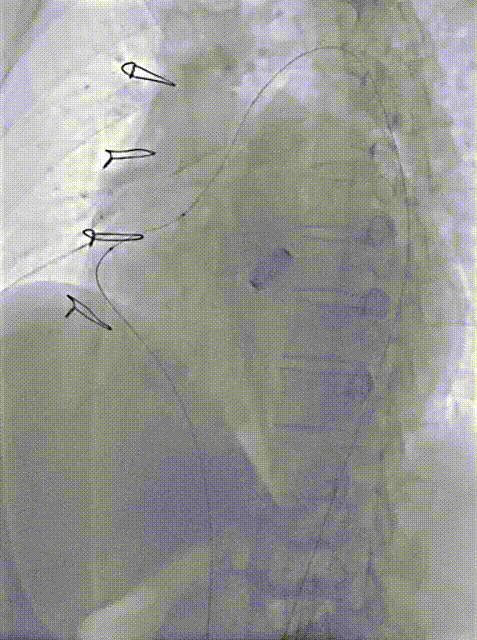

术中操作

4.对于Aortic Wrapping吻合口漏,应优选入口出口双伞封堵,有利于术后包裹腔快速机化消除分流。